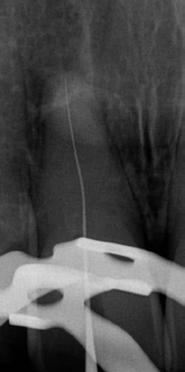

1. a–f ábrák: A cingulumon keresztül gömbfúróval kialakított hozzáférés a trepanációs kavitás labiális irányba történő túlzott mértékű kiterjesztését eredményezheti, és ez lényegesen növelheti a perforáció esélyét (a). A guttapercha átsejlik a lágyrészek alatt (b). Klinikailag igazolt perforáció (c). A preoperatív sagittális irányú CBCT-szeleten jól látható a labiális perforáció (d). Labiális irányú perforáció (fekete nyíl; e). A tényleges gyökércsatorna (piros nyíl; f).

5. a–l. ábrák: Az incisális élen keresztül kialakított hozzáférés lehetővé teszi a pericervikális dentin megőrzését. Kalcifikáció esetén CBCT-felvétel készítése hasznosnak bizonyulhat a hozzáférési nyílás tervezése során (a–d) . Minden fog koronai helyreállítása a gyökértömés elkészítésével egyidejűleg történt. A négyéves (e–h) és a kétéves (i–l) kontrollok alkalmával készített röntgenfelvételeken teljes gyógyulás látható. Mindkét fog tünetmentes és funkcióképes volt. (Dr. Viraj Vora esetei)

kialakítása során fennáll a fog labiális irányú perforációjának veszélye, mivel ilyenkor a foganyag elvételét labiális irányú fúrótartással kezdjük. Nemrégiben újragondolták a

sálisabb megközelítéssel javasolták. 21,22 Az új ajánlásban azt javasolják, hogy a frontfogakban történő hozzáférési nyílás kialakítását a cingulumtól távolabb, inkább az incizális él közelében kezdjük meg 19. Ez lehetővé teszi a lehető legtöbb pericervikális dentin megőrzését és kizárólag a legszükségesebb mennyiségű dentin kerül eltávolításra. Emellett ez a kialakítás a cingulumon keresztül történő hozzáféréshez képest egyenesebb hozzáférést biztosít a labiális és a linguális, vagy palatinális csatornákhoz, valamint lehetővé teszi a csatornák hatékonyabb tisztítását. 21 A fogak kopása esetén a hozzáférést az incisális „felszín” közepén alakítjuk ki (3. a-b ábrák) . A frontfogak kezelése során a megfelelő fúró kiválasztása is kiemelkedően fontos szereppel bír. A korábban ajánlott gömbfúrók használata ma már kifejezetten kontraindikáltnak számít. A gömbfúrók használatakor jellemzően egy fordított tölcsér alakú üreg kerül kialakításra. Ezekben az esetekben az üreg egyre szélesebb lesz, ahogy egyre mélyebbre hatolunk a fúrónkkal (2. a-b ábrák) 23 A gömbfúrók helyett olyan fúrók használata javasolt, amellyel elkerülhető lehet a trepanációs kavitás túlzott mértékű kiterjesztése, és amely segítségével a hozzáférési nyílás legszűkebb részét a pericer -

vikális dentin területének megfelelően tudjuk kialakítani (4. ábra) 19 Ezáltal képesek vagyunk a lehető legnagyobb volumenű pericervikális dentinállomány (PCD) megőr -

zésére. Ez azért fontos, mert a frontfogak funkcionális megterhelése során – a PCD-nek megfelelően elhelyezkedő területben – jelentős stressz ébred (5. a–l ábrák) 24 Szükség esetén egy CBCT-felvételt is készíthetünk. A 3D-s adatok jelentős mértékben segíthetik a klinikus munkáját a gyökércsatorna koronális vetületének vizualizálásában, és ennek alapján az egyenes vonalú hozzáférés biztosításához szükséges belépési pont meghatározásában (5.